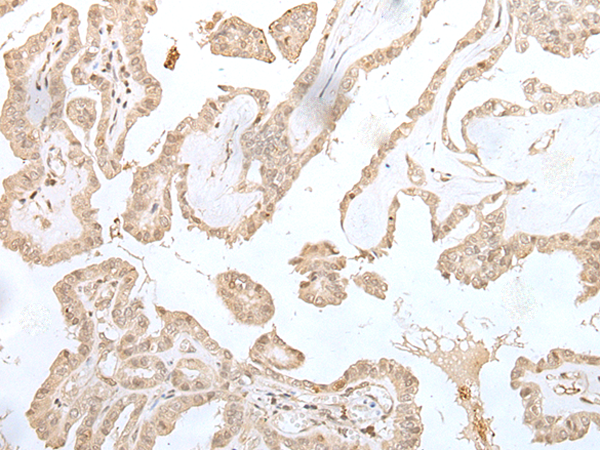

IHC positive control: |

Human gastric cancer and human thyroid cancer |

IHC Recommend dilution: |

25-100 |